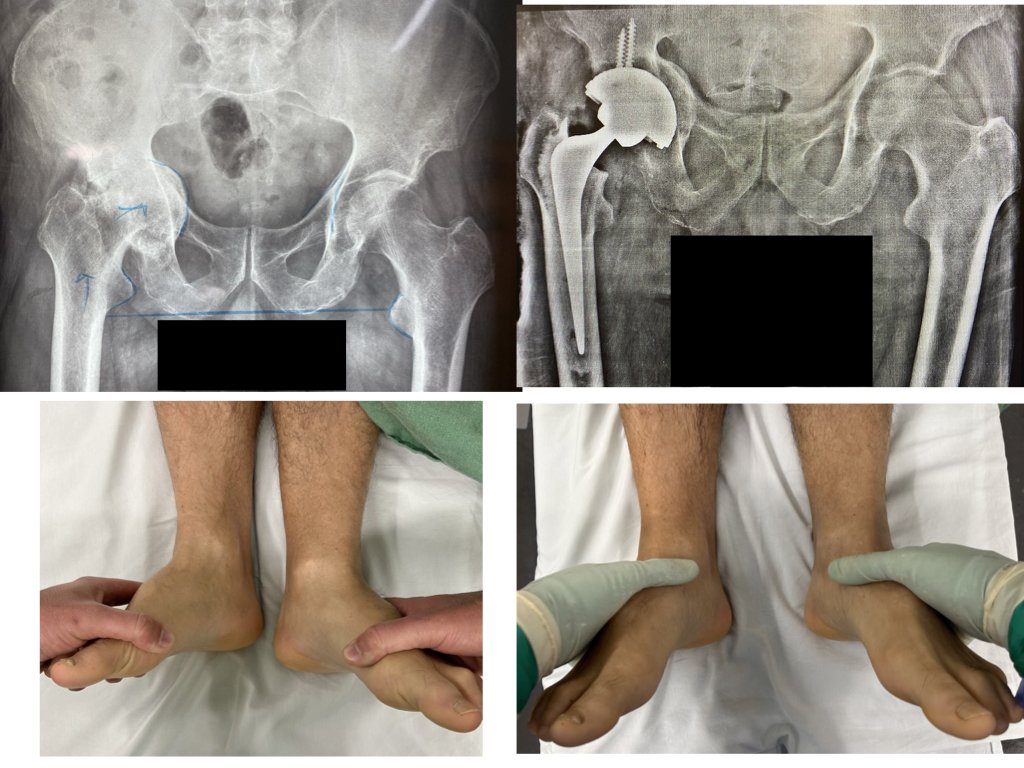

9. Alterações Estruturais e Discrepância de Comprimento

O aparecimento de discrepância no comprimento dos membros inferiores indica progressão de dano cartilaginoso para destruição óssea. O colapso da cabeça femoral e a erosão acetabular resultam em alteração do alinhamento esquelético global, com a pelve adaptando-se à nova geometria articular.

Esta fase representa transição crítica. Enquanto a perda isolada de cartilagem permite várias abordagens terapêuticas, o comprometimento ósseo estrutural limita significativamente as opções. Quanto maior for o atraso após início de alterações ósseas, maior a complexidade cirúrgica, podendo exigir enxertos ósseos, implantes especializados ou procedimentos reconstrutivos adicionais.

[caption id align="alignnone" width="1024"]

Correção da diferença de comprimento devido à artrose severa do quadril direito com uso de enxerto, parafusos e implante especial no acetábulo. [/caption]